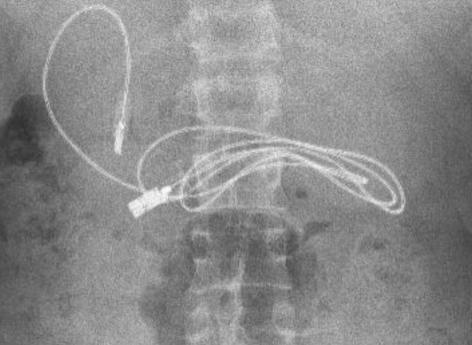

Selon le tabloïd anglais, l’adolescent, originaire de la ville de Diyarbakir en Turquie, a commencé à s’inquiéter après de violents maux de ventre et des nausées. Il s’est donc rendu à l’hôpital, où on lui a fait une radiographie pour comprendre l’origine du mal. Et là, grosse surprise pour les internes. Sur la radio, dans l'estomac, ils découvrent un câble de près d’un mètre de long qui convient à la recharge des téléphones ou des casques audios. Une chance : il n’est pas encore digéré. Pour faire face à cette situation assez insolite, le garçon est transféré à l’hôpital universitaire Firat d’Elazig, situé à environ trois heures de route de là, afin de voir un spécialiste, le gastro-entérologue pédiatrique Yasar Dogan.

Le Dr Dogan a procédé à une endoscopie pour retirer le câble de charge. Il s’agit d’une technique qui permet d’observer l'œsophage, l'estomac et le duodénum, grâce à un tube souple contenant une petite caméra afin d’effectuer des prélèvements et des gestes chirurgicaux. Il a déclaré aux médias locaux : "Nous avons évidemment eu du mal à retirer le câble, car une extrémité du câble était passée dans l'intestin grêle." En plus du câble, les médecins ont également du retirer un élastique à cheveux qui se trouvait aussi dans l'estomac de l'adolescent. Heureusement, cette aventure ubuesque finit bien : la procédure a été un succès et le jeune patient a pu être renvoyé chez lui en bonne santé.